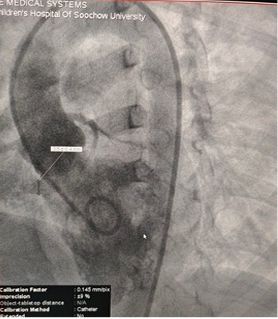

Successful Closure of Multi-Exit Membranous Septal Aneurysm-Type VSD Using MemoSorb Fully Biodegradable Occluder

Base diameter: ~6.1 mm with multiple exit points

Membrane-like tissue observed over the defect

Color Doppler: Left-to-right shunt flow

Diagnosis: Perimembranous VSD

Challenge: Multiple exits + fragile membrane tissue

Selected MemoSorb ABFDQ-II 9 occluder based on intraoperative angiography and echocardiographic assessment.